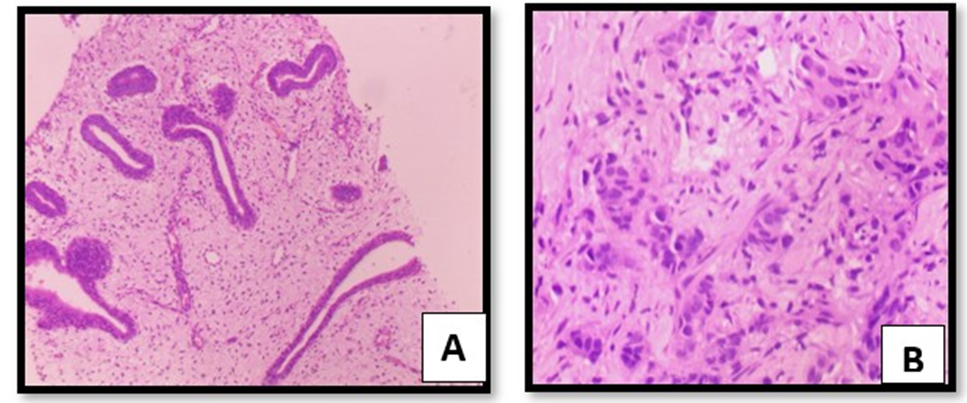

The molecular findings were further confirmed by histopathological study, after simple staining with H & E staining as shown in figure 4A (normal) that showing proliferating and differentiating ductal parenchyma cells. These cellular changes initiate shrinkage followed by reduction in cell-size perhaps due to apoptosis. These changes are responsible morphology of the ductal carcinoma during metastasis as shown in figure 4B. Simillarly, the frequency of EpCAM and MTHFR 677T, both the gene showing highest frequency in of expression in ductal carcinoma during metastasis in breast cancer patients with respect to controls.

Figure 4AB: Showing breast parenchyma with cystic dilatation and showing normal proliferation of dusts in control tissue (fig4A) and invasive ductal carcinoma with Grade III (3+3+1).